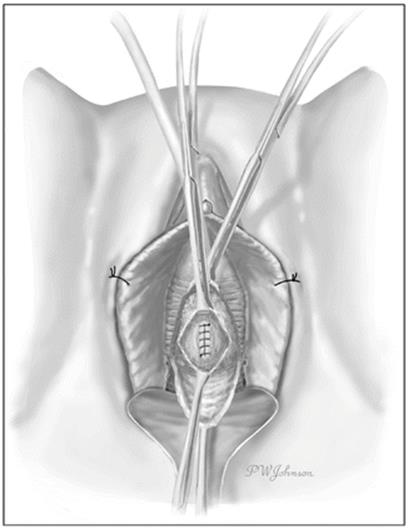

The Foley catheter is usually seen following complete excision of UD (Fig. 11.9). The urethra can be reconstructed over as small as a 12F Foley catheter without long term risk of urethral stricture [1] and should be closed in a watertight fashion with running or interrupted 4.0 synthetic absorbable suture. The closure should be tension-free and water tight (Fig. 11.10). In rare circumstances, a UD may extend circumferentially around the urethra and require segmental resection of the involved portion of the urethra and complex reconstruction [3, 65].

Fig. 11.10

The urethra is closed with absorbable suture (Used with permission from Rovner ES. Urethral diverticula. In: Female Urology, 3rd ed. Edited by Raz S, Rodriguez LV. Philadelphia: Saunders Elsevier; 2008)